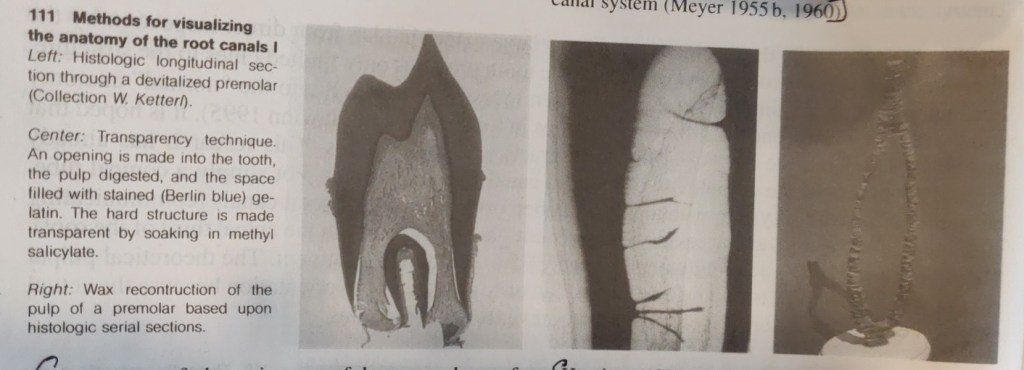

The first detailed systematic description of root canal anatomy found in the literature is by Carabelli (1844). The same manner of representation with longitudinal and transverse sections in different planes is still used in modern textbooks (eg., Cohen and Burns 1994). Some of these illustrations go back to the original sections and serial sections (Black 1902; Miller 1904). In addition to direct observation with the unaided eye and the microscope, the chemical dissolution method has provided much valuable information. In this process the tooth is opened, the pulp digested, and the empty pulp space filled. The famous Swiss pulp researcher Hess (1917) perfected this technique in which he filled the pulp space with vulcanized India rubber and then dissolved the surrounding tooth substance with 50% hydrochloric acid. This acid dissolution preparation showed the complex branching of the pulp tissues and, with it, the root canal system. Whereas the previous sections, slides, and drawings were only two-dimensional, now for the first time it was possible to see a spatial representation of the entire root canal system. Hess studied 2800 teeth of the permanent human dentition and his student Zurcher (1922) studied deciduous teeth. Together they gathered statistical data on the number of canals and their ramifications.

Most techniques require the destruction of the tooth. However, at the beginning of the twentieth century the transparency method was developed (Adolf 1913) in which the integrity of the tooth and the spatial relationships of the root canal and its outer contours were preserved. Various substances (from colored gelatin and paraffin to silicone) were introduced into the pulp space through an access opening, and the tooth was then made transparent by means of oil of cedar, benzol, salicylic acid compounds.

While histologic sections have long provided information on the structure of the root canal and the pulp tissue, Meyer (1955-1970) set new standards. From special sections of all 16 types of permannet teeth he made 50x scale models of the apical canals (the last 6 mm of each) of 800 teeth by projecting the circumference of the canals and building wax models layer by layer. This study further clarified the complexity of the pulp space, from then on called the root canal system (Meyer 1955 b, 1960).